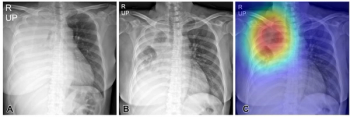

An emerging deep learning algorithm can reportedly triage 40 percent of no-change X-rays while providing 88 to 90 percent accuracy for detecting changes with X-rays obtained in the emergency department and intensive care unit at a tertiary referral hospital, according to recently published research.